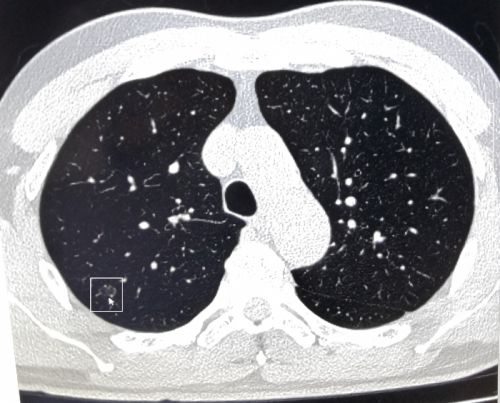

张先生体检时肺部ct筛查影像显示有可疑结节(箭头处)。

复查肺穿刺活检,确诊张先生为早期“微小浸润性肺腺癌”。

近日,长沙57岁的张先生到湖南省人民医院岳麓山院区健康管理中心做健康体检时提出,胃肠道有些不适,想做胃肠镜等项目。中心主任李慧根据其咳嗽症状、吸烟史和年龄等因素,建议增加肺部CT项目。张先生觉得没必要,经过李慧主任耐心解释后欣然接受,结果CT显示“右上肺可见大小约8×6mm结节”,建议跟踪复查,每半年一次。

李慧主任看了检查结果后非常重视,要求中心回访医生缩短标准回访跟踪间隔时间。一个月后,工作人员进行电话回访时,建议张先生到健康管理中心肺结节门诊就诊。看门诊时,医生给张先生复查了低剂量高清晰肺部增强CT,显示右上肺结节较上次变大,立即安排肺穿刺活检,确诊为“早期微小浸润性肺腺癌”。幸运的是,由于回访跟踪及时,尚属肺癌早期。住院做了根治手术后,张先生目前状态良好。